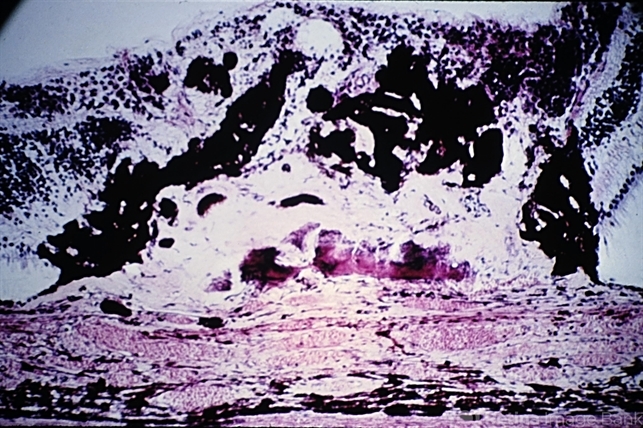

- disciform macular lesion, hyperplasia, retinal pigment epithelium

- Disciform macular lesion with marked hyperplasia of RPE (A.F.I.P. No. 797119).